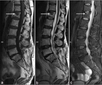

Tanı YöntemleriAtipik hemanjiomun tanısı genellikle görüntüleme yöntemleriyle konur. Bu yöntemler arasında:

Bu görüntüleme yöntemleri, hemanjiomun boyutunu, konumunu ve yapısını belirlemek için kullanılır. Ayrıca, doktorlar histolojik inceleme için biyopsi de alabilirler. Tedavi SeçenekleriAtipik hemanjiom tedavisi, hastanın genel durumu, tümörün boyutu ve belirtilerin şiddeti gibi faktörlere bağlı olarak değişiklik gösterir. Tedavi seçenekleri arasında:

MRG ve BT gibi görüntüleme yöntemleri tanı ve takipte oldukça güvenilirdir. Cerrahi müdahale genellikle sadece şu durumlarda gündeme gelir: şiddetli ağrı, nörolojik defisit riski, patolojik kırık tehlikesi veya hızlı büyüme. Mevcut tedavi seçenekleri arasında gözlem, embolizasyon, radyofrekans ablasyon ve cerrahi yer alır.